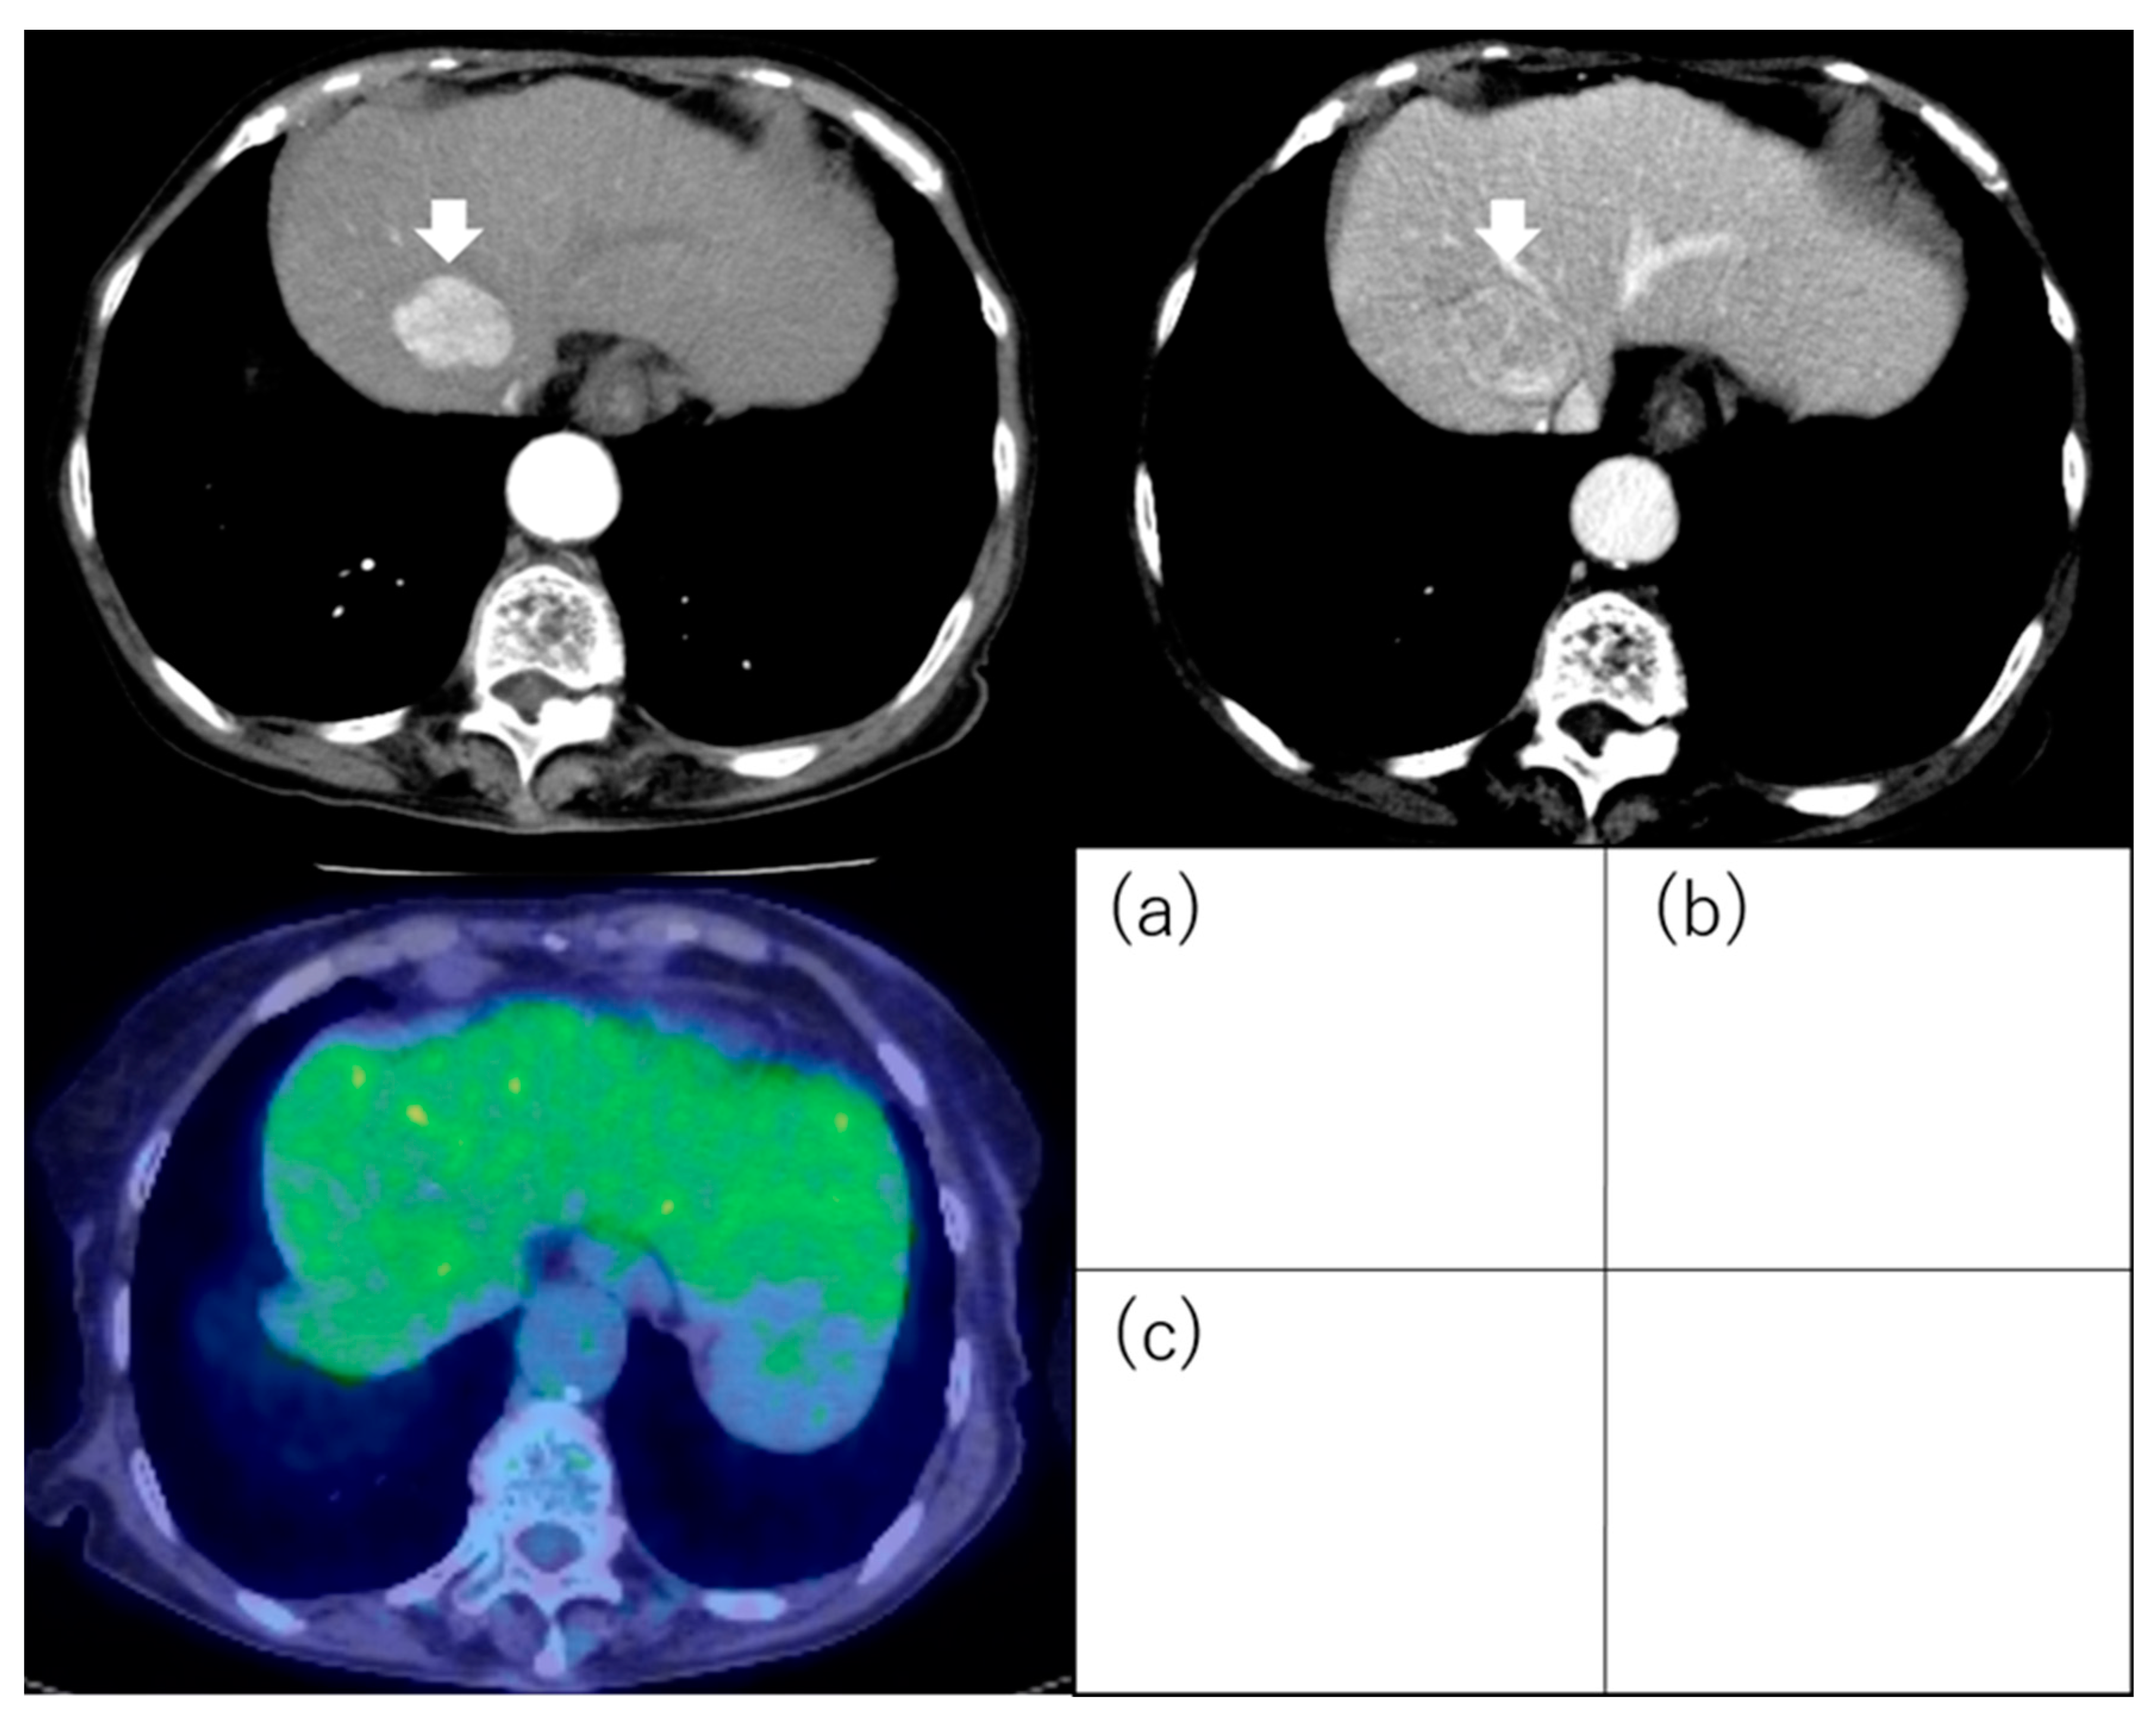

3. Contrast-Enhanced Computed Tomography

3.1. Enhancement Pattern in the Arterial Phase

3.2. Intratumoral Arteries and Enhancement Pattern

- Kawamura, Y.; Ikeda, K.; Hirakawa, M.; Yatsuji, H.; Sezaki, H.; Hosaka, T.; Akuta, N.; Kobayashi, M.; Saitoh, S.; Suzuki, F.; et al. New classification of dynamic computed tomography images predictive of malignant characteristics of hepatocellular carcinoma. Hepatol. Res. Off. J. Jpn. Soc. Hepatol. 2010, 40, 1006–1014. [Google Scholar] [CrossRef]

- Kawamura, Y.; Ikeda, K.; Seko, Y.; Hosaka, T.; Kobayashi, M.; Saitoh, S.; Kumada, H. Heterogeneous type 4 enhancement of hepatocellular carcinoma on dynamic CT is associated with tumor recurrence after radiofrequency ablation. AJR Am. J. Roentgenol. 2011, 197, W665–W673. [Google Scholar] [CrossRef]

- Nakachi, K.; Tamai, H.; Mori, Y.; Shingaki, N.; Moribata, K.; Deguchi, H.; Ueda, K.; Inoue, I.; Maekita, T.; Iguchi, M.; et al. Prediction of poorly differentiated hepatocellular carcinoma using contrast computed tomography. Cancer Imaging Off. Publ. Int. Cancer Imaging Soc. 2014, 14, 7. [Google Scholar] [CrossRef] [PubMed]

- Shimizu, R.; Tamai, H.; Mori, Y.; Shingaki, N.; Maeshima, S.; Nuta, J.; Maeda, Y.; Moribata, K.; Muraki, Y.; Deguchi, H.; et al. The arterial tumor enhancement pattern on contrast-enhanced computed tomography is associated with primary cancer death after radiofrequency ablation for small hepatocellular carcinoma. Hepatol. Int. 2016, 10, 328–339. [Google Scholar] [CrossRef] [PubMed]

| Kawamura et al. [40] | 191 | Solitary and ≤3 cm | Resection (60) RFA (131) | Outcome (recurrence) | The type 4 enhancement pattern was an independent factor for recurrence (HR, 27.68; 95% CI, 6.82–112.33; p < 0.001). |

| Nakachi et al. [41] | 223 | Early stage | Biopsy Resection | Differentiation | HCC with enhancement with non-enhanced area predicted poorly differentiation. Predictive value as follows; sensitivity was 85%, specificity was 76%, positive predictive value was 93%, negative predictive value was 97%, and accuracy was 77%. |

| Shimizu et al. [42] | 226 | ≤3 tumors and ≤3 cm | RFA | Outcome (recurrence, OS) | Heterogeneous enhancement pattern was one of the independent factors for critical recurrence (HR, 2.753; 95% CI, 1.453–5.219; p = 0.002) and related cancer death (HR, 2.369; 95% CI, 1.187–4.726; p = 0.014). |